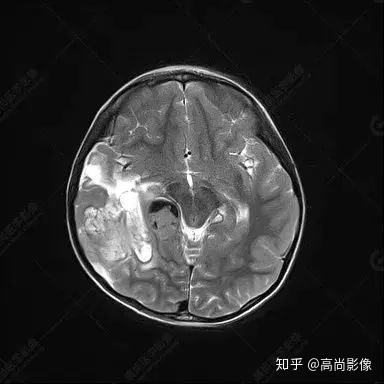

右側(cè)顳葉腫瘤切除術(shù)后(具體不詳):右側(cè)顳部骨質(zhì)不連續(xù)呈術(shù)后改變,右側(cè)顳葉術(shù)區(qū)見片狀長T1長T2信號影,F(xiàn)LAIR呈低信號;術(shù)區(qū)后方右側(cè)顳枕葉見一巨大占位性病變影,邊界欠清,大小約6.2×5.8×4.3cm(前后×左右×上下),信號不均勻,T1WI呈等稍低信號間雜少許高信號,T2WI呈高稍低混雜信號,DWI示部分病灶彌散受限,相應(yīng)ADC圖減低,磁敏感序列見部分呈極低信號,增強(qiáng)掃描可見明顯不均勻強(qiáng)化,鄰近硬腦膜及小腦幕增厚并明顯強(qiáng)化;另延髓右前方及右側(cè)橋小腦角區(qū)見一不規(guī)則形異常信號影,大小約3.2×1.3×3.7cm(左右×前后×上下),呈長T1稍長T2信號,F(xiàn)LAIR呈等信號,DWI未見受限,增強(qiáng)后明顯均勻強(qiáng)化,鄰近腦膜明顯強(qiáng)化。鄰近腦實質(zhì)及右側(cè)顳角明顯受壓;左側(cè)大腦半球未見局灶性信號異常,中線結(jié)構(gòu)稍左移。

右側(cè)顳葉腫瘤切除術(shù)后:現(xiàn)術(shù)區(qū)后方右側(cè)顳枕葉及延髓右前方占位,右側(cè)顳枕部硬腦膜及小腦幕明顯強(qiáng)化,結(jié)合既往影像資料,考慮為胚胎源性惡性腫瘤,如非典型畸胎樣/橫紋肌樣瘤(AT/RT)或原始神經(jīng)外胚層腫瘤(PNET)。

非典型畸胎樣/橫紋肌樣瘤(AT/RT) 是一種高度惡性中樞神經(jīng)系統(tǒng)腫瘤,臨床罕見,臨床表現(xiàn)無特異性,好發(fā)于 5 歲以下兒童,尤以 3 歲以下多見,在兒童原發(fā)性中樞神經(jīng)系統(tǒng)(CNS)腫瘤中占 1%~3%。該腫瘤體積一般較大,幕上大于幕下,有明顯的占位效應(yīng)。該腫瘤成分復(fù)雜,囊變、出血、壞死常見。因此 AT/RT信號混雜,囊性部分呈 T1WI低、T2WI高信號,增強(qiáng)后不強(qiáng)化;若瘤體出血,囊內(nèi)可見T1WI稍高信號、T2WI低信號,實性部分在 T1WI上呈混雜等、低信號,在T2WI 及 T2-FLAIR上呈混雜等高信號,增強(qiáng)掃描后大部分呈環(huán)形條帶樣明顯強(qiáng)化,中心壞死區(qū)不強(qiáng)化。另外,該腫瘤實性成分在DWI上呈高信號,說明腫瘤細(xì)胞核密集,水分子擴(kuò)散明顯受限,提示該腫瘤惡性程度高,容易復(fù)發(fā)及轉(zhuǎn)移。